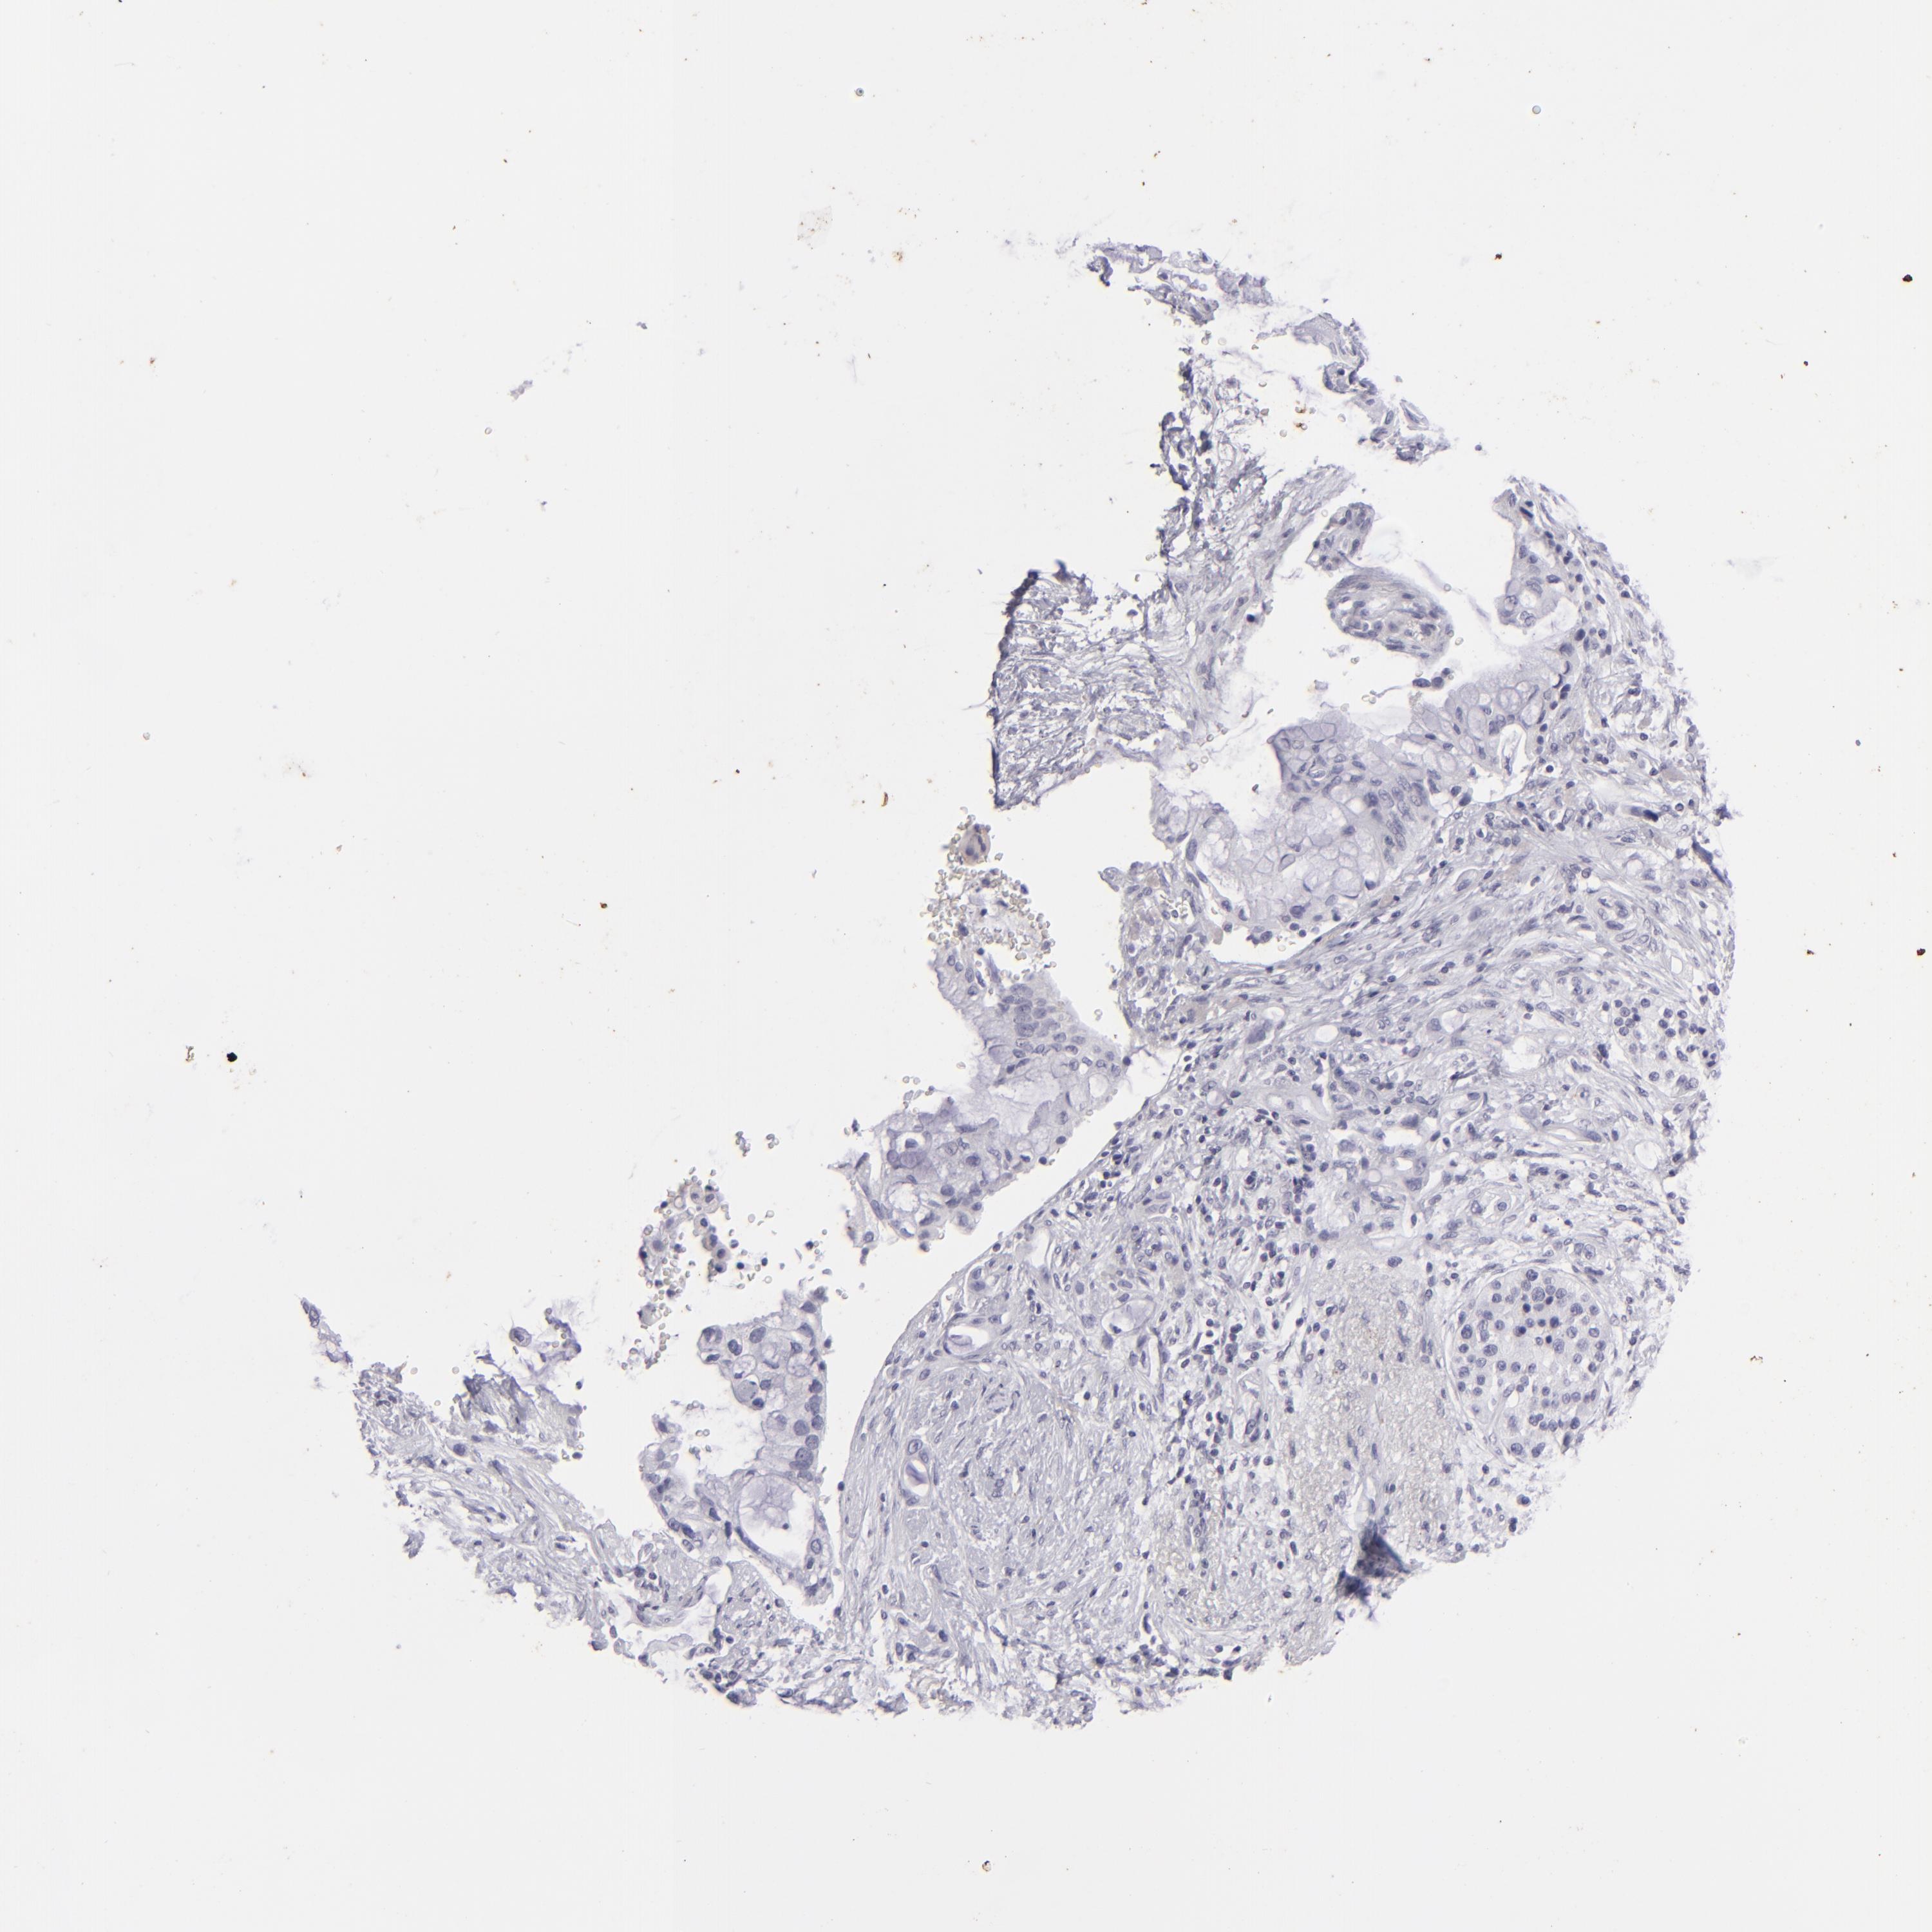

PANCREATIC CANCER - Protein expressioni

A mouse-over function shows sample information and annotation data. Click on an image to view it in a full screen mode. Samples can be filtered based on level of antibody staining by selecting one or several of the following categories: high, medium, low and not detected. The assay and annotation is described here.

Note that samples used for immunohistochemistry by the Human Protein Atlas do not correspond to samples in the TCGA dataset.

Antibody stainingi

Antibody staining in the annotated cell types in the current human tissue is reported as not detected, low, medium, or high, based on conventional immunohistochemistry profiling in selected tissues. This score is based on the combination of the staining intensity and fraction of stained cells.

Each image is clickable and will lead to virtual microscopy that enables deeper exploration of all samples and also displays staining intensity scores, fraction scores and subcellular localization as well as patient and tissue information for each sample.

Antibody HPA017917

Antibody HPA062908

Antibody CAB002153

Adenocarcinoma, NOS